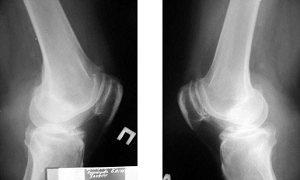

Рентгенологический метод обследования.

Рентгеновские снимки коленного сустава в обязательном порядке выполнялись всем пациентам. Подавляющее большинство больных обращались к нам, уже имея на руках рентгенограммы, выполненные в других учреждениях. В этих случаях дополнительных рентген-снимков делать не приходилось.

Рентгенологически в острой стадии тендопериостопатии надколенника патологических изменений в области связки практически не определяется. В хронической стадии выявляется склероз кортикального слоя патологически измененного полюса надколенника, а в далеко зашедших случаях - неровности или остеофиты на нижнем или верхнем полюсе надколенника, что свидетельствует о длительности патологического процесса на почве хронического нарушения местного кровообращения и расстройства метаболизма тканей, т. е. развиваются уже явления деформирующего артроза в бедренно- надколенниковом суставе (пателло-феморальный артроз).

Деформирующий артроз коленного сустава, пателло-феморальный артроз. Пациентка К., 50 лет. Выявляется склероз кортикального слоя патологически измененного полюса надколенника.

При сопоставлении клинических и рентгенологических данных выявляется определенная закономерность. Так, при выраженной клинической симптоматике, болевой синдром обусловлен асептическим воспалением в местах развития дистрофического процесса, и рентгенологическая картина может быть нормальной. В дальнейшем, когда происходит обызвествление связки, более четко проявляются и рентгенологические признаки в виде дополнительных участков обызвествления у края кости.

Плотность этих участков небольшая и их выявление требует целенаправленного поиска. Контуры кости становятся нечеткими, форма и размеры участков обызвествлений могут быть самыми разнообразными, но локализация этих участков обызвествления всегда топографически соответствует местам прикрепления к кости сухожилий или связок и совпадает с их направлением.

На этапе, когда обызвествлённый участок связки начинает замещаться костью, на снимке появляются участки оссификации, определяемые по образующейся костной структуре. Обычно на этой стадии снижается выраженность клинической симптоматики. В то же время на снимках четко видны значительные по объему и распространенности участки оссификации, имеющие, неровные контуры и различную форму в виде шипов, крючков и т.д., а также усиление контуров связки, увеличение рентгенологической плотности.